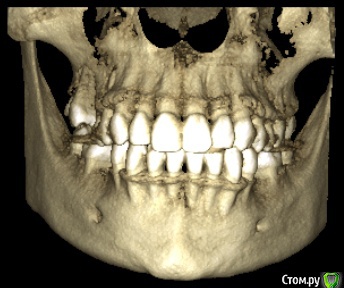

marilinka Опубликовано 28 февраля, 2016 Поделиться Опубликовано 28 февраля, 2016 Уважаемые доктора! Дело в том, что 1 марта у меня назначена имплантация нижних 5, которых никогда не было, первичная адентия. Верхняя 5 с одной стороны сильно опустилась, ортопед предложил, убрать ее под коронку, предварительно обточив, чтобы хватило места для коронки. И все бы ни чего,если бы буквально в течение недели ситуация во рту не поменялась бы, передние зубы стали упираться в друг друга, не сильно и не всегда, как зубки "поставишь", есть ощущение, что на снимках норм прикус, а сейчас занижен. Присутствуют болевые ощущения в скулах и висках, щеки пропали и самое страшное появилась носогубка. Доктор по поводу этого говорит, что протезируемся именно для этого, чтобы разгрузить сустав. В чем собственно мой вопрос хватит ли места для нижней пятерки, с той стороны где нет 2 зубов? Есть ли занижение прикуса и как с этим быть если есть? Не усугубит ли имплантация состояние внчс? Может стоит сделать новый снимок, слепки, которые кстати не делали и отложить пока имплантацию, раз у меня есть ощущение изменений во рту? С доктором общалась только по телефону, когда начало это беспокоить, раньше 1числа в больницу не попаду, нахожусь в 200 км от нее. Доктору доверяю, про таких как он говорят золотые руки, в паре с ним ортопед кмн. Что смогла то прикрепила. Ссылка на комментарий

marilinka Опубликовано 28 февраля, 2016 Автор Поделиться Опубликовано 28 февраля, 2016 (изменено) http://s017.radikal.ru/i416/1602/ea/fce843bb39a7t.jpghttp://s019.radikal.ru/i631/1602/80/8cf8f17bcc98t.jpghttp://s017.radikal.ru/i431/1602/78/b66e5d9610f7t.jpghttp://s019.radikal.ru/i616/1602/61/7ccb6dbbeb23t.jpg Изменено 28 февраля, 2016 пользователем marilinka Ссылка на комментарий

marilinka Опубликовано 28 февраля, 2016 Автор Поделиться Опубликовано 28 февраля, 2016 Ну вот как то вот так зубки во рту находятся. Ссылка на комментарий

Lolopop Опубликовано 28 февраля, 2016 Поделиться Опубликовано 28 февраля, 2016 добрый вечер, места для пятерки хватит, действительно-имеется небольшой наклон следующего зуба в сторону отсутсвующего, имплантация на состояние внчс не повлияет, делайте смело Ссылка на комментарий